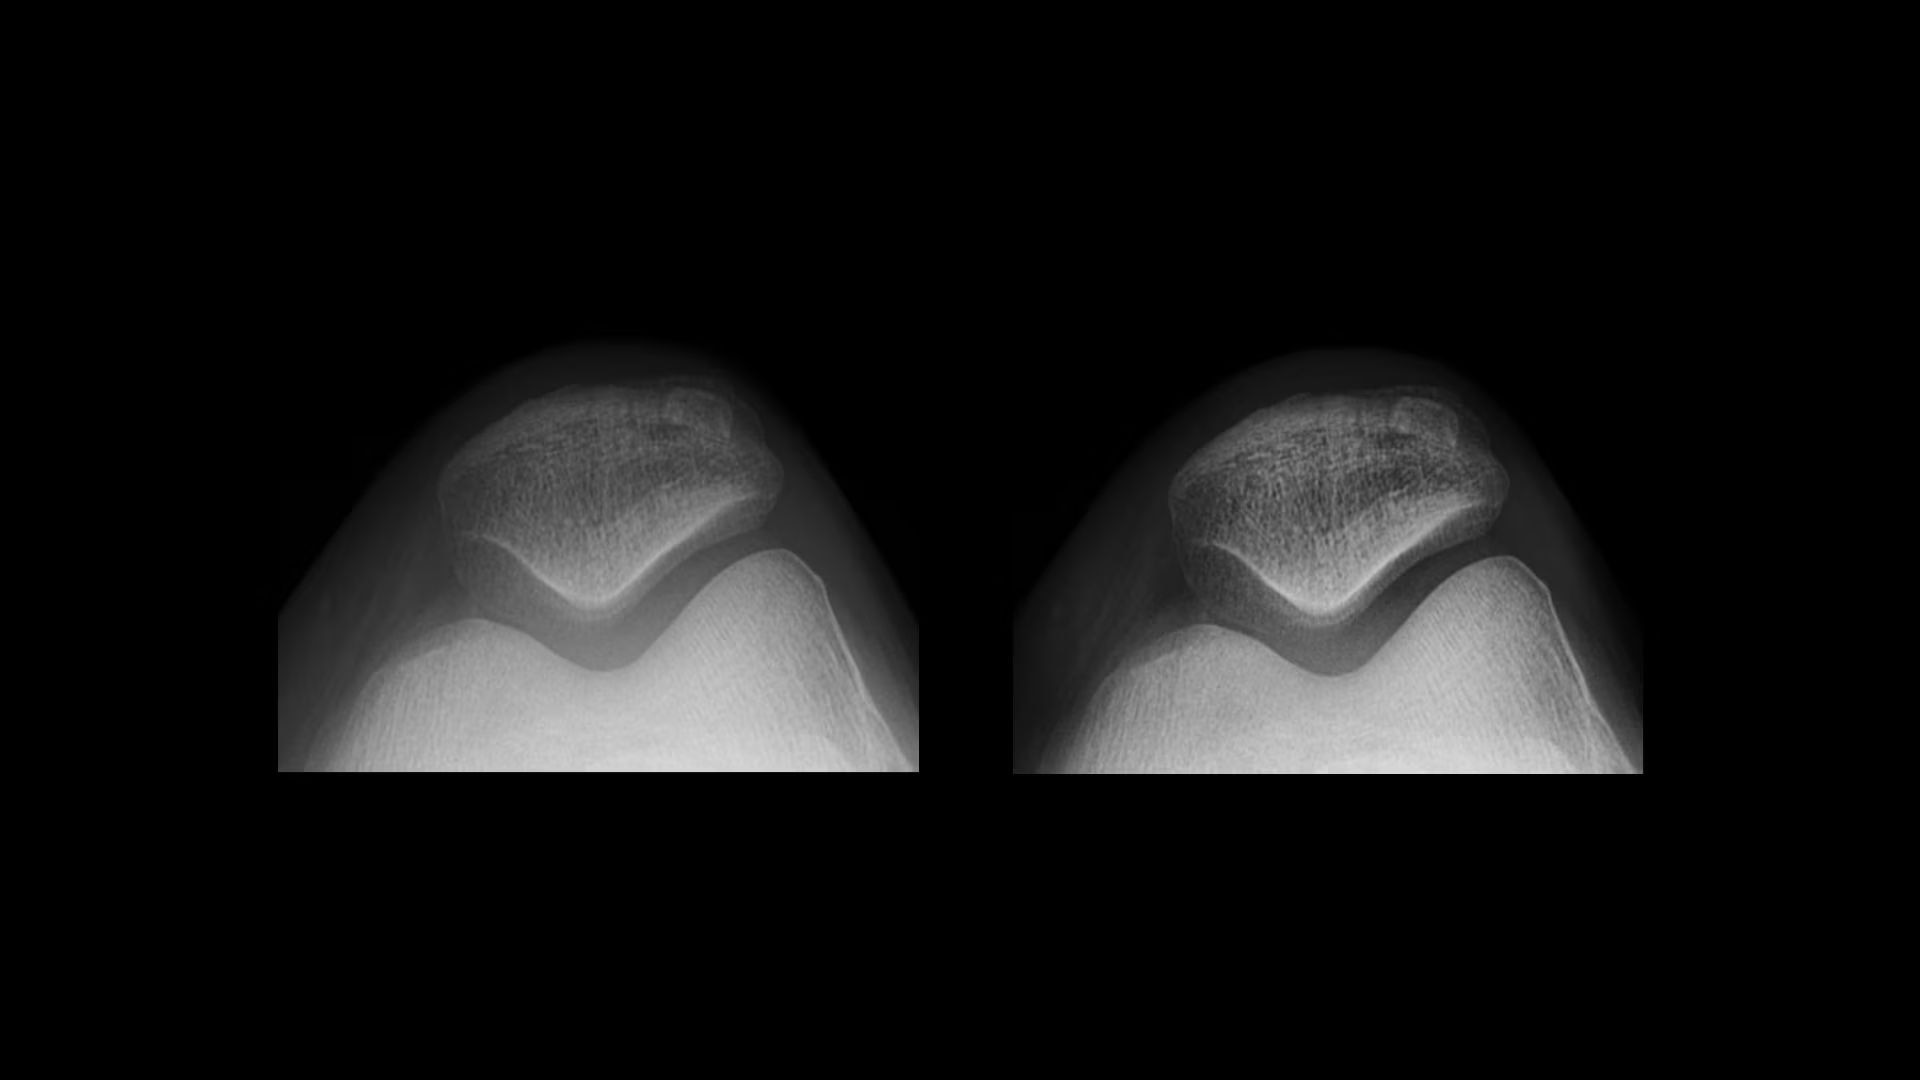

Exceptional detail

Acheive outstanding clarity and anatomical detail across image types

Extraordinary anatomical detail at low dose

Helix™ Advanced Image Processing offers unparalleled sharpness, balanced contrast, and optimal brightness, even in the face of dose and patient anatomy variations, as well as challenging metal implants. Available on all of our fixed and mobile X-ray systems, Helix provides consistent performance regardless of exposure technique or exam conditions.

Reduced noise

Reduce noise levels

Detail Preserving Noise Reduction Filter (DPNR) offers significant noise reduction capabilities while minimizing the effect on fine details. DPNR provides adaptive noise reduction based on the image with an edge-preserving filter to maintain edge details. It has three levels of reduction (low, medium and high).

web-helix-3-noise-ci-en